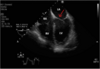

The image below is from the transoesophageal echocardiogram of an adult patient who is about to undergo cardiac surgery. The structure labelled with the arrow is the: TOE image - four chamber, with arrow pointing to leaflet closest to septum A) Anterior mitral leaflet B) Posterior mitral leaflet C) Tricuspid septal leaflet D) Tricuspud anterior leaflet E) Tricuspid posterior leaflet

A) Anterior mitral leaflet RV is an anterior structure hence anterior leaflet